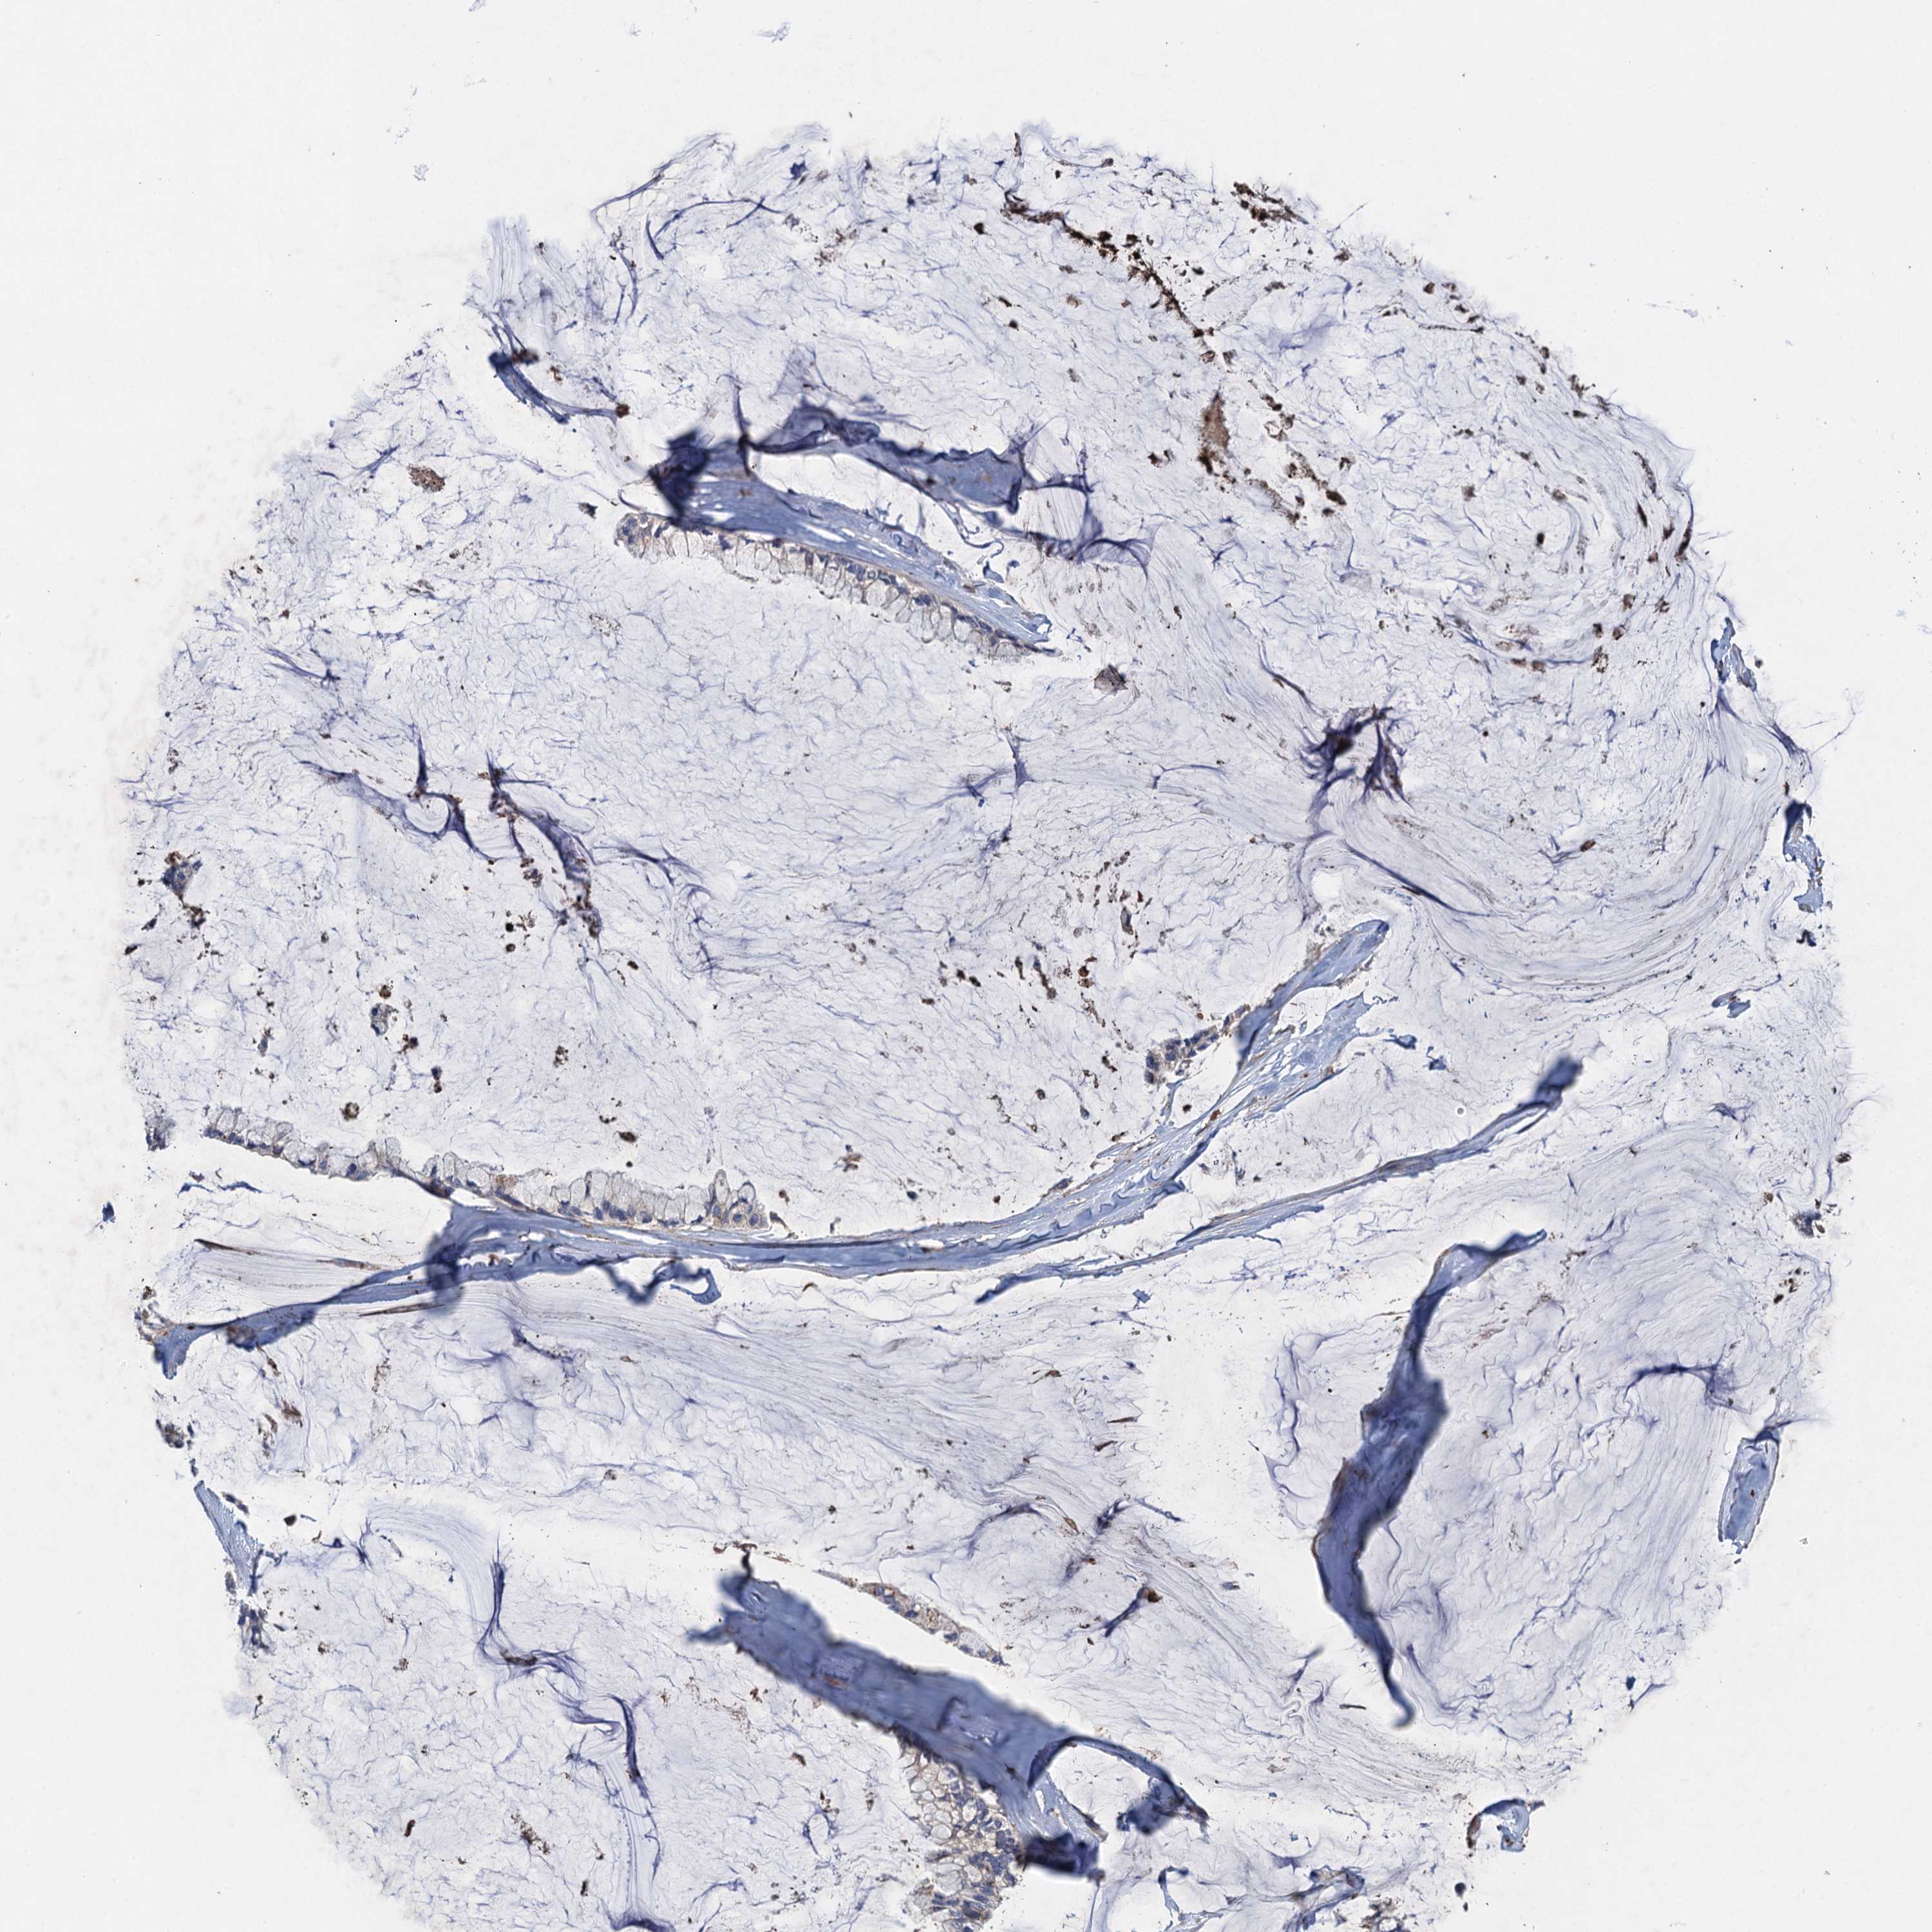

OVARIAN CANCER - Protein expressioni

A mouse-over function shows sample information and annotation data. Click on an image to view it in a full screen mode. Samples can be filtered based on level of antibody staining by selecting one or several of the following categories: high, medium, low and not detected. The assay and annotation is described here.

Note that samples used for immunohistochemistry by the Human Protein Atlas do not correspond to samples in the TCGA dataset.

Antibody stainingi

Antibody staining in the annotated cell types in the current human tissue is reported as not detected, low, medium, or high, based on conventional immunohistochemistry profiling in selected tissues. This score is based on the combination of the staining intensity and fraction of stained cells.

Each image is clickable and will lead to virtual microscopy that enables deeper exploration of all samples and also displays staining intensity scores, fraction scores and subcellular localization as well as patient and tissue information for each sample.

Antibody HPA041174

Antibody HPA041390

Cystadenocarcinoma, serous, NOS

Carcinoma, endometroid

Cystadenocarcinoma, mucinous, NOS

Carcinoma, NOS